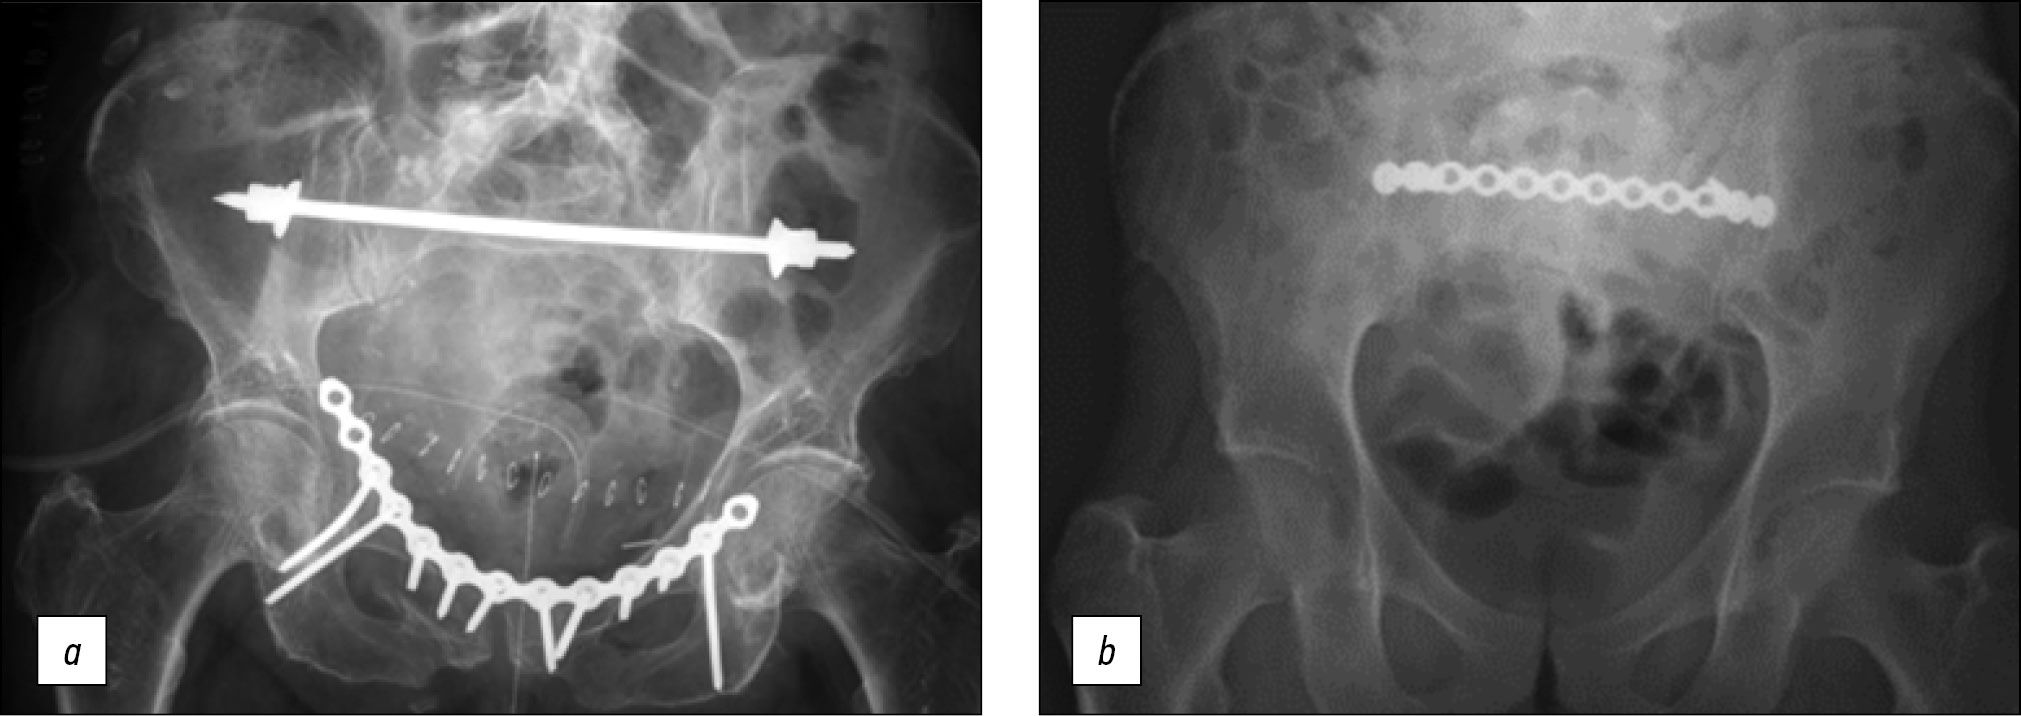

Транссакральные импланты являются альтернативными транскутанными методиками, при которых имплант с длинной резьбой проходит полностью через коридор SI или SII до контралатеральной подвздошной кости [38]. Системы трансподвздошной мостовидной фиксации представляют собой минимально инвазивную фиксацию левой и правой подвздошной кости. Они представлены балками (рис. 7, a), пластинами (рис. 7, b) или стержнями, соединяющими педикулярные винты, и проводятся подкожно по задней поверхности крестца с помощью двух минидоступов в проекции левой и правой подвздошной кости, выполняя роль внутренних фиксаторов подвздошной кости [39].

Рис. 7. Системы трансподвздошной мостовидной фиксации [19, 39]. a — обзорная рентгенограмма таза, демонстрирующая трансподвздошную мостовидную фиксацию заднего полукольца таза балкой, b — обзорная рентгенограмма таза, показывающая трансподвздошную мостовидную фиксацию заднего полукольца таза пластиной.